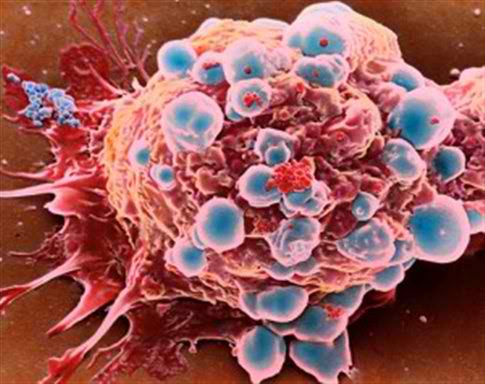

CategoryΕρευνητές της Ιατρικής Σχολής του Πανεπιστημίου Case Western Reserve στις ΗΠΑ ανακάλυψαν μια μεταλλαγμένη μορφή του γονιδίου Chk1, που όταν εκφράζεται στα καρκινικά κύτταρα, σταματά μόνιμα τον πολλαπλασιασμό τους και προκαλεί κυτταρικό θάνατο χωρίς την ανάγκη οποιουδήποτε χημειοθεραπευτικού σχήματος. Η μελέτη καταλήγει σε ένα πρωτοφανές εύρημα, δηλαδή ότι η τεχνητή ενεργοποίηση του γονιδίου Chk1 είναι ικανή να εξοντώσει τα καρκινικά κύτταρα. «Εντοπίσαμε έναν νέο δρόμο στην αντικαρκινική θεραπεία και ελπίζουμε να μας βοηθήσει να μειώσουμε την τοξικότητα των θεραπειών του καρκίνου, συγκριτικά πάντα με την χημειοθεραπεία και την ακτινοθεραπεία», τονίζει ο Δρ Γιουγουέι Ζανγκ, επίκουρος καθηγητής του Τμήματος Φαρμακολογίας και επικεφαλής της μελέτης. «Αξιοποιώντας τα συμπεράσματα της μελέτης, οι επιστήμονες στο μέλλον θα μπορέσουν να σταματούν τον πολλαπλασιασμό των καρκινικών κυττάρων, διορθώνοντας τα κυτταρικά και γενετικά λάθη», υπογραμμίζει. Ο Δρ Ζανγκ και οι συνεργάτες του μελετώντας τους βασικούς μηχανισμούς της ακεραιότητας του γονιδίωματος, τυχαία ανακάλυψαν την μεταλλαγμένη εκδοχή του γονιδίου…

Ραδιενεργά νανοσωματίδια από χρυσό και χημικές ουσίες που περιέχονται στο τσάι, μπορούν να συρρικνώσουν έως 80% τους όγκους του καρκίνου του προστάτη σε πειραματόζωα, αποτελώντας έτσι μία εν δυνάμει εναλλακτική θεραπεία με λιγότερες παρενέργειες για τους ανθρώπους σε σχέση με την παραδοσιακή χημειοθεραπεία, η οποία έχει τοξικές επιπτώσεις στον οργανισμό, καθώς πλήττει παράλληλα και υγιή ζωτικά όργανα. Οι ερευνητές της Ιατρικής Σχολής του Πανεπιστημίου του Μισούρι, με επικεφαλής τους Δρ Κατές Κάτι και Κάθι Κάτλερ, που δημοσίευσαν τη μελέτη στο επιστημονικό έντυπο Proceedings of the National Academy of Sciences (PNAS), ανακοίνωσαν ότι βρήκαν ένα πιο αποτελεσματικό και ασφαλή τρόπο να επιτίθενται στους όγκους, αξιοποιώντας νανοσωματίδια χρυσού και ουσίες που εξάγουν από τα φύλλα του τσαγιού. Η νέα θεραπεία απαιτεί χιλιάδες φορές μικρότερες δόσεις από την χημειοθεραπεία και δεν κάνει ζημιά σε άλλα όργανα και κύτταρα. Σύμφωνα με τους ερευνητές, μία συγκεκριμένη ουσία του τσαγιού έλκεται από τα καρκινικά κύτταρα του…